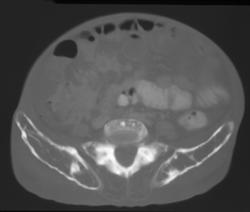

Diagnosis

Joint Effusion Elbow Joint